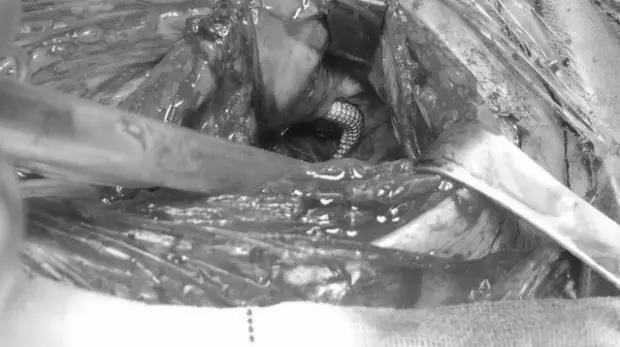

王兵教授主刀、崔文军副主任、吴斐、安乾、司江涛等医师紧密配合,在手术麻醉科胡强夫主任团体的保驾护航下,手术成功实施。术中小心翼翼的切开皮肤、皮下组织,分离出左颈总及颈内外动脉起始段,探查瘤体巨大,虽然“敌人”近在咫尺之间,但医生们仍不能贸然行动,于是采取最稳妥的方案。先从患者左颈总动脉穿刺,反复尝试顺利将导丝引入左颈内动脉远端,并成功植入2枚覆膜支架,先行封堵动脉瘤破口,造影明确无造影剂外渗后切开假性动脉瘤体,取出大量混合性血栓。

让人意想不到,也是无比惊险的一幕出现了,医生们赫然看到支架在瘤腔内穿过,支架的2/3是在血管外走行,就像是在破裂的颈动脉两端架起了一座“桥梁”——这是生命之桥!看到这一幕,大家都感到后怕,若贸然切开瘤体或支架向远端少放1cm,则患者再无手术机会,生存机会渺茫。(图3、图4、图5、图6)

图3

图4

图5

图6